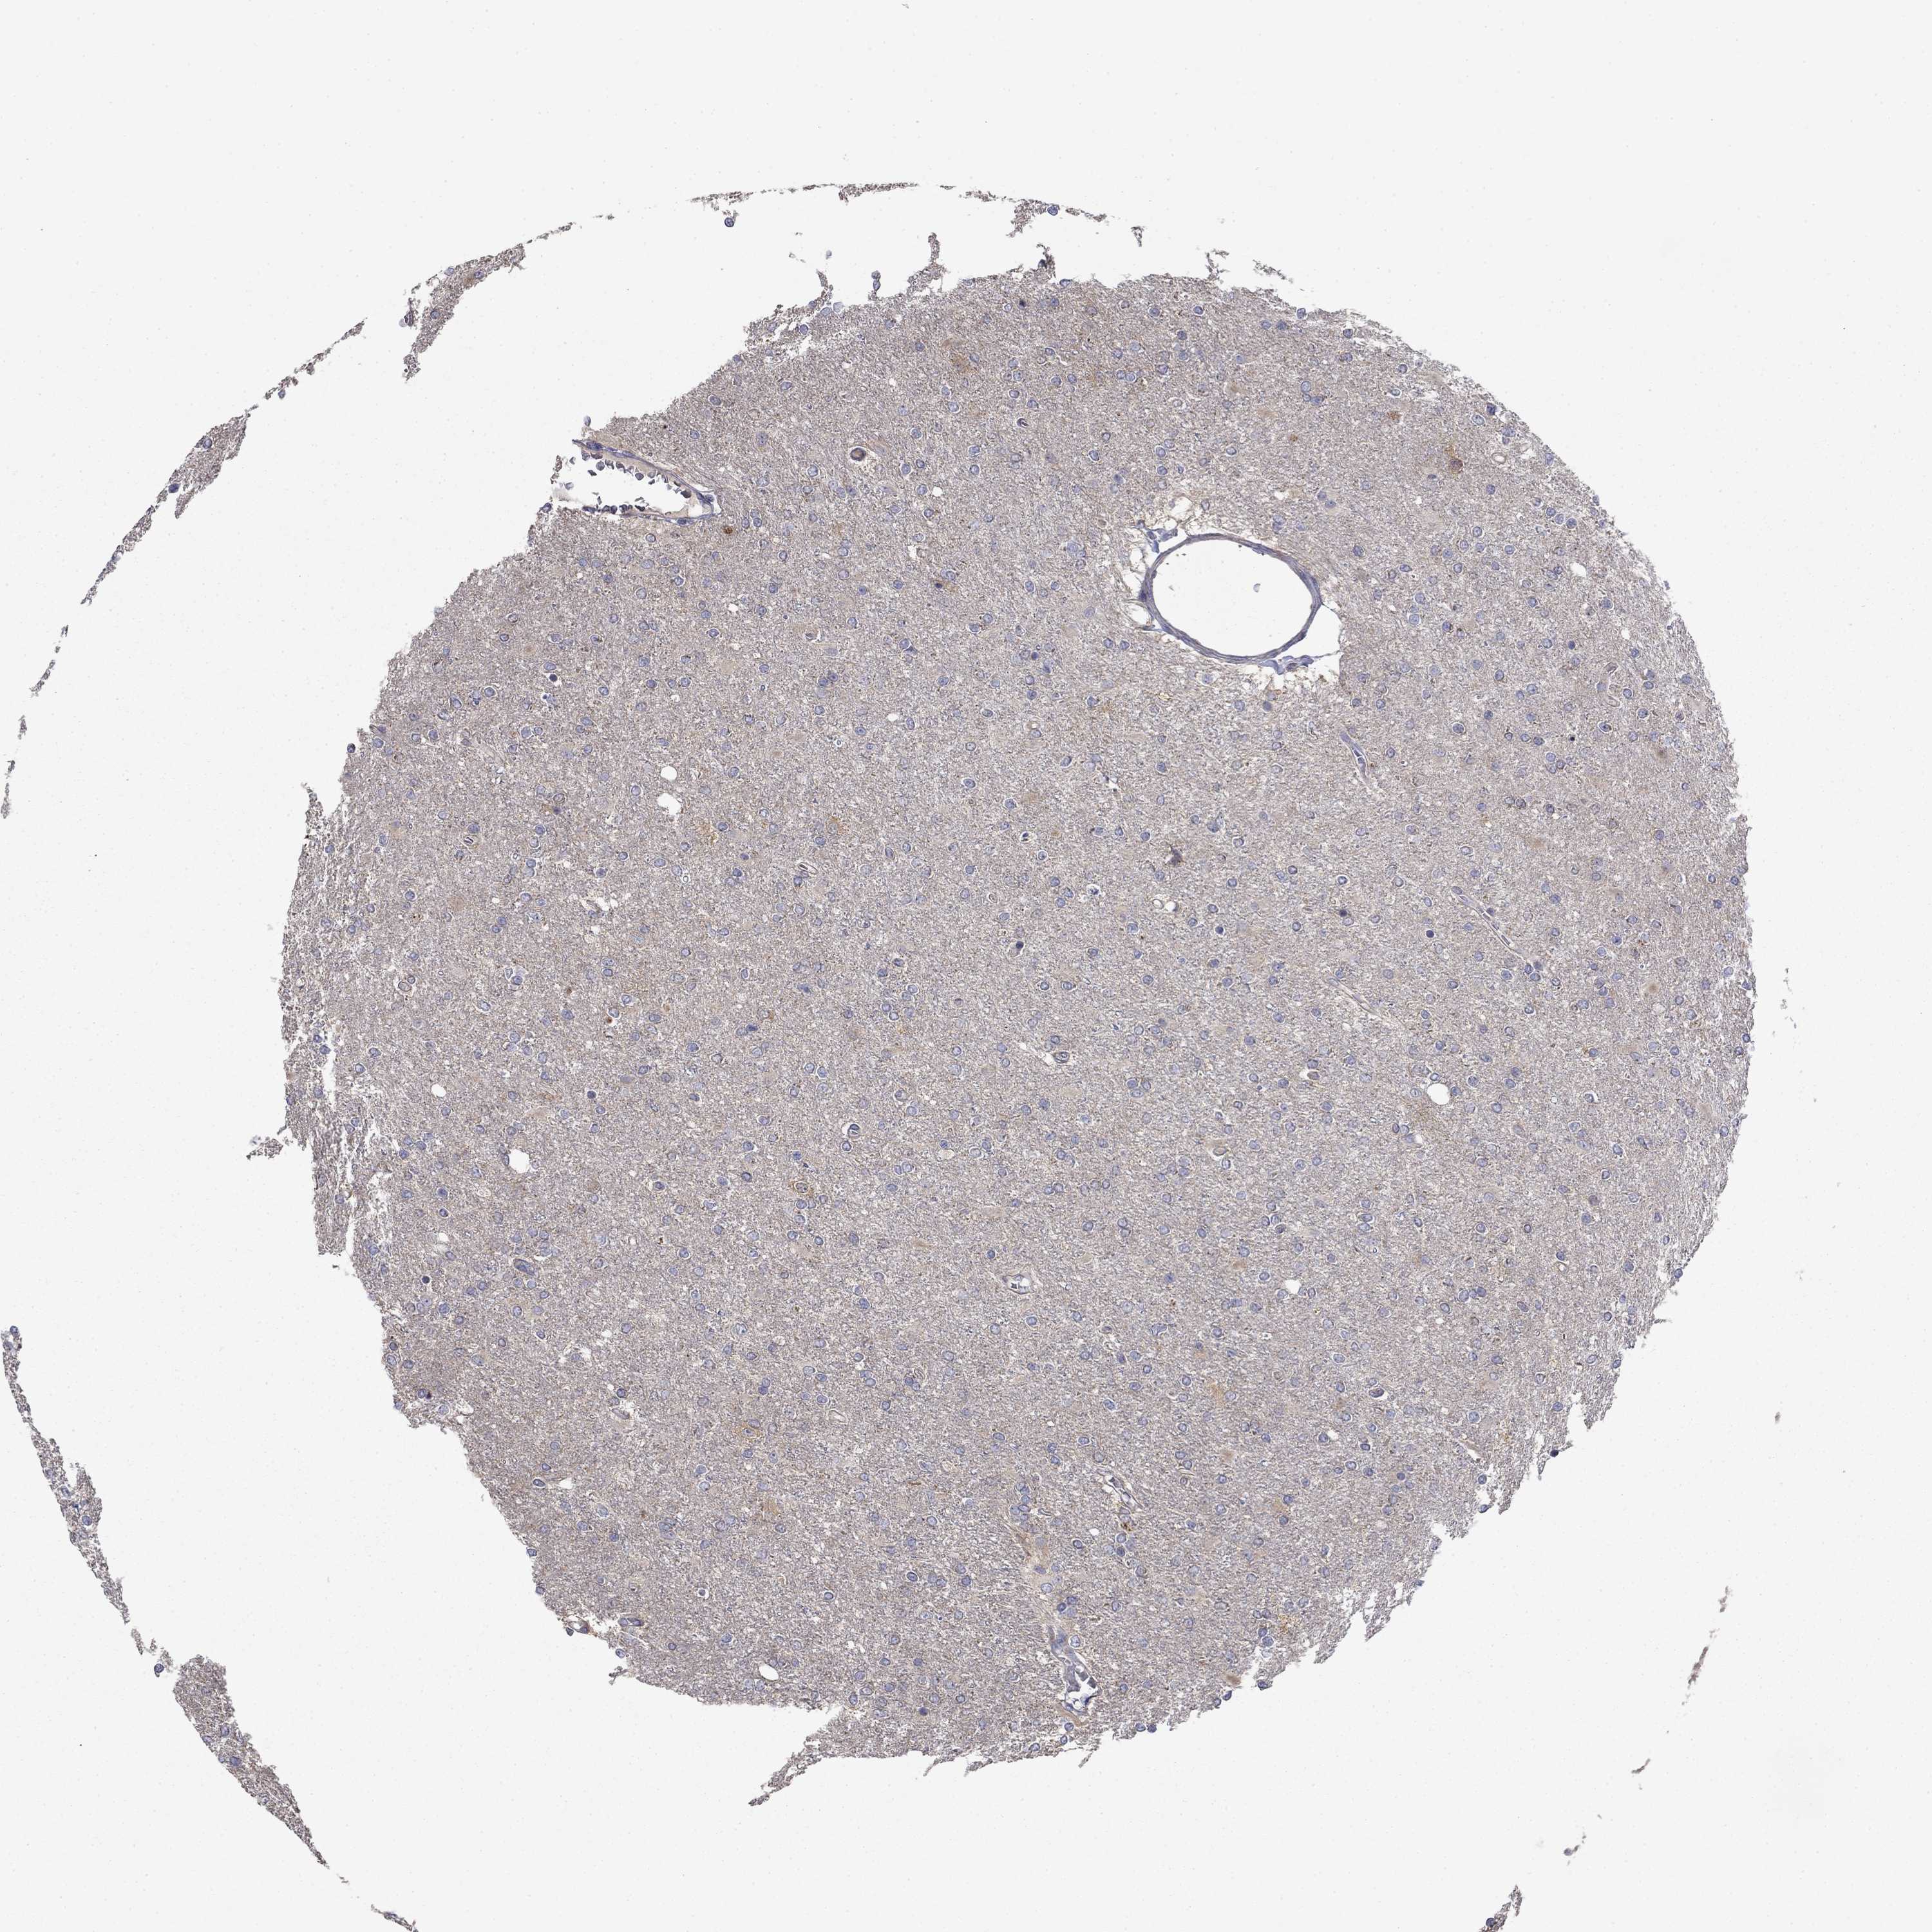

GLIOMA - Protein expressioni

A mouse-over function shows sample information and annotation data. Click on an image to view it in a full screen mode. Samples can be filtered based on level of antibody staining by selecting one or several of the following categories: high, medium, low and not detected. The assay and annotation is described here.

Note that samples used for immunohistochemistry by the Human Protein Atlas do not correspond to samples in the TCGA dataset.

Antibody stainingi

Antibody staining in the annotated cell types in the current human tissue is reported as not detected, low, medium, or high, based on conventional immunohistochemistry profiling in selected tissues. This score is based on the combination of the staining intensity and fraction of stained cells.

Each image is clickable and will lead to virtual microscopy that enables deeper exploration of all samples and also displays staining intensity scores, fraction scores and subcellular localization as well as patient and tissue information for each sample.

Antibody HPA058187

Staining

High

Medium

Low

Not detected

Intensity

Strong

Moderate

Weak

Negative

Quantity

>75%

75%-25%

<25%

None

Location

Nuclear

Cytoplasmic/membranous

Cytoplasmic/membranous,nuclear

Glioma, malignant, Low grade

Glioma, malignant, High grade

Glioma, malignant, NOS